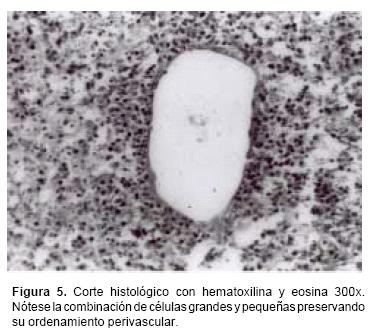

Los estudios histopatológicos han demostrado que los LPSNC en pacientes IC son muy similares a los que se presentan en los pacientes VIH–positivos. Con microscopia a menor aumento se demuestra el patrón de infiltración angiocéntrico, formándose collares de células tumorales alrededor de los pequeños vasos sanguíneos con diferentes cantidades de depósitos de reticulina.14 En casos avanzados se llega a perder este ordenamiento perivascular y las células tienden a invadir el parénquima cerebral circundante, ya sea en forma de compactos agregados o como una infiltración difusa de células tumorales similar a la encefalitis.15 Se ha informado con frecuencia reacción astrocítica que en ocasiones tiende a ser muy marcada,16 así como áreas de necrosis coagulativa. Todo esto explica el motivo por el cual con mucha frecuencia estas lesiones son confundidas en el estudio transoperatorio con astrocitomas, glioblastomas multiformes o metástasis.17

Los resultados de las biopsias realizadas por estereotaxia, mostraron que sólo en tres pacientes el diagnóstico histológico transoperatorio correspondió a linfoma, y en el resto fue confundido con astrocitomas, metástasis o glioblastomas multiformes. En el análisis de las biopsias por microscopia de luz a menor aumento fue posible observar un patrón de infiltración angiocéntrico, formando collares de células tumorales rodeando pequeños vasos cerebrales (Figura 4). Con mayor aumento fue posible observar con más detalle el cúmulo de células, en donde en algunos casos consistió en una combinación de células grandes y pequeñas pero persistiendo el ordenamiento perivascular (Figura 5). Sin embargo, en los pacientes con estadios más avanzados de la enfermedad se apreció pérdida del ordenamiento perivascular, con invasión de las células tumorales al parénquima cerebral. También se observó reacción astrocítica asociada, además de la presencia de macrófagos. La mayoría de los tumores fueron considerados de la variedad de células grandes difusas, de acuerdo a la Clasificación Revisada Europea–Americana de Linfoma (REAL),27 y en un solo caso correspondió a la variedad anaplásica. Por inmuhistoquímica, el total de los tumores resultaron positivos a los antígenos CD20 y CD79A, por lo que se consideraron de células B.